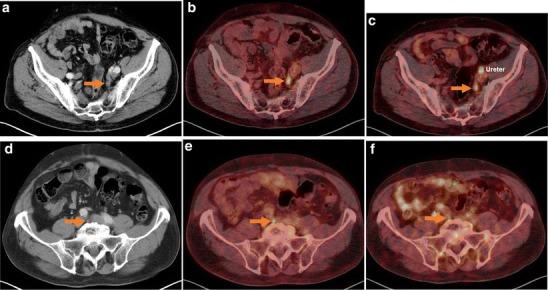

In 14 selected patients with PSA relapse of prostate cancer, [(18)F]DCFPyL PET/X-ray computed tomography (CT) was performed in addition to [(68)Ga]Ga-PSMA-HBED-CC PET/CT. A systematic comparison was carried out between results obtained with both tracers with regard to the number of detected PSMA-positive lesions, the standardized uptake value (SUV)max and the lesion to background ratios.

RESULTS

All suspicious lesions identified by [(68)Ga]Ga-PSMA-HBED-CC were also detected with [(18)F]DCFPyL. In three patients, additional lesions were observed using [(18)F]DCFPyL PET/CT. The mean SUVmax in the concordant [(18)F]DCFPyL PSMA-positive lesions was significantly higher as compared to [(68)Ga]Ga-PSMA-HBED-CC (14.5 vs. 12.2, p = 0.028, n = 15). The mean tumor to background ratios (n = 15) were significantly higher for [(18)F]DCFPyL compared to [(68)Ga]Ga-PSMA-HBED-CC using kidney, spleen, or parotid as reference organs (p = 0.006, p = 0.002, p = 0.008), but no significant differences were found using the liver (p = 0.167) or the mediastinum (p = 0.363) as reference organs.

在14例选定的前列腺癌PSA复发患者中,除了进行[(68)Ga]Ga-PSMA-HBED-CC PET/CT外,还进行了[(18)F]DCFPyL PET/X射线计算机断层扫描(CT)。对两种示踪剂获得的结果在检测到的PSMA阳性病变数量、标准化摄取值(SUV)最大值和病变与背景比值方面进行了系统比较。

结果

[(68)Ga]Ga-PSMA-HBED-CC识别出的所有可疑病变也能用[(18)F]DCFPyL检测到。在3例患者中,使用[(1)F]DCFPyL PET/CT观察到了额外的病变。与[(68)Ga]Ga-PSMA-HBED-CC相比,[(18)F]DCFPyL PSMA阳性病变中的平均SUV最大值显著更高(14.5对12.2,p = 0.028,n = 15)。以肾脏、脾脏或腮腺作为参考器官时,[(18)F]DCFPyL的平均肿瘤与背景比值(n = 15)显著高于[(68)Ga]Ga-PSMA-HBED-CC(p = 0.006,p = 0.002,p = 0.008),但以肝脏(p = 0.167)或纵隔(p = 0.363)作为参考器官时未发现显著差异。